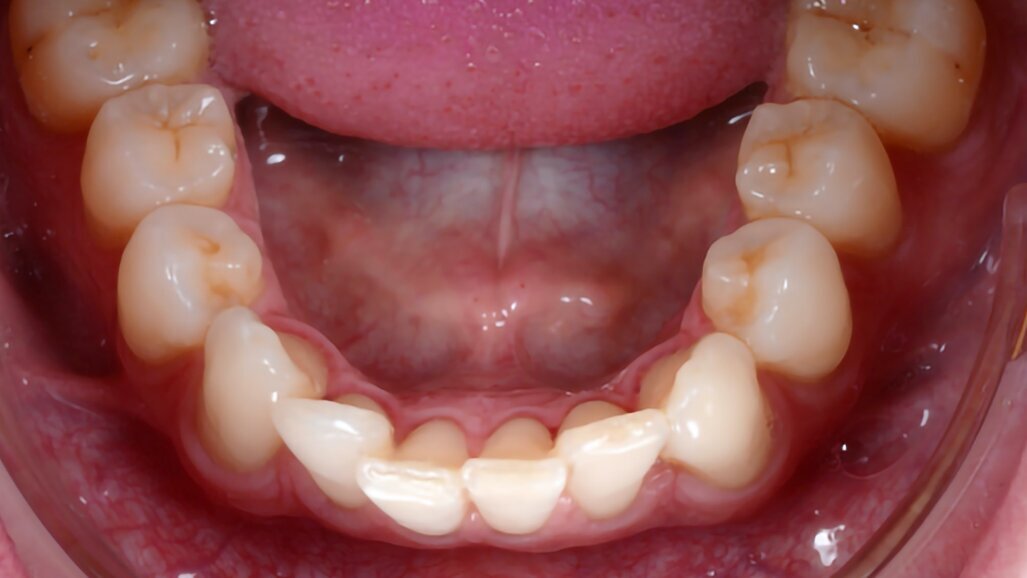

Fig. 3: Before (left) and after (right). The case was solved over four months with 16 clear aligners

(Smilers) and photobiomodulation therapy (with the ATP38), applied every week for six minutes every time aligners were changed.